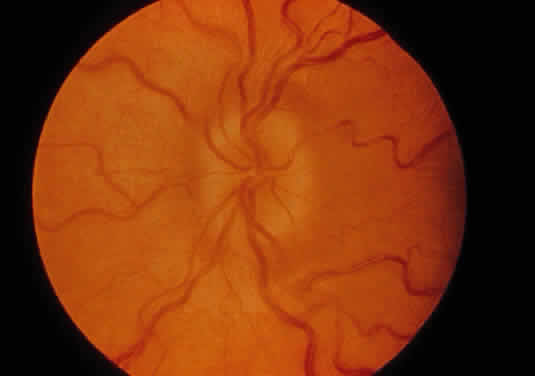

Corneal clouding (Fig. 10), hyperopic astigmatism, and a mild retinopathy with surface-wrinkling maculopathy (Fig. 11) appear to be the constant ocular triad.75 Some patients have retinal vascular tortuosity, optic nerve head swelling (Fig. 12), visual field defects, and abnormalities in color vision. Visual complaints are uncommon.

Fig. 12. Optic nerve head swelling in a patient with mucolipidosis III. (Traboulsi E, Maumenee I: Ophthalmologic findings in mucolipidosis III. Am J Ophthalmol 102:529, 1986)